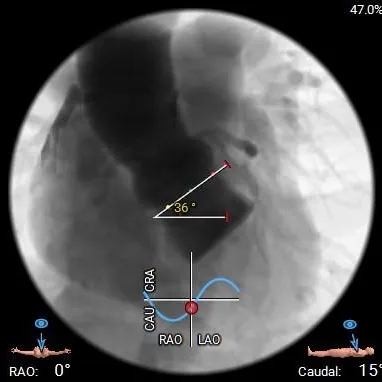

水平夹角36°非横位心,弓角、弓距可,弓部散在钙化,预估输送器可顺利过弓、跨瓣;

瓣环水平夹角:44°